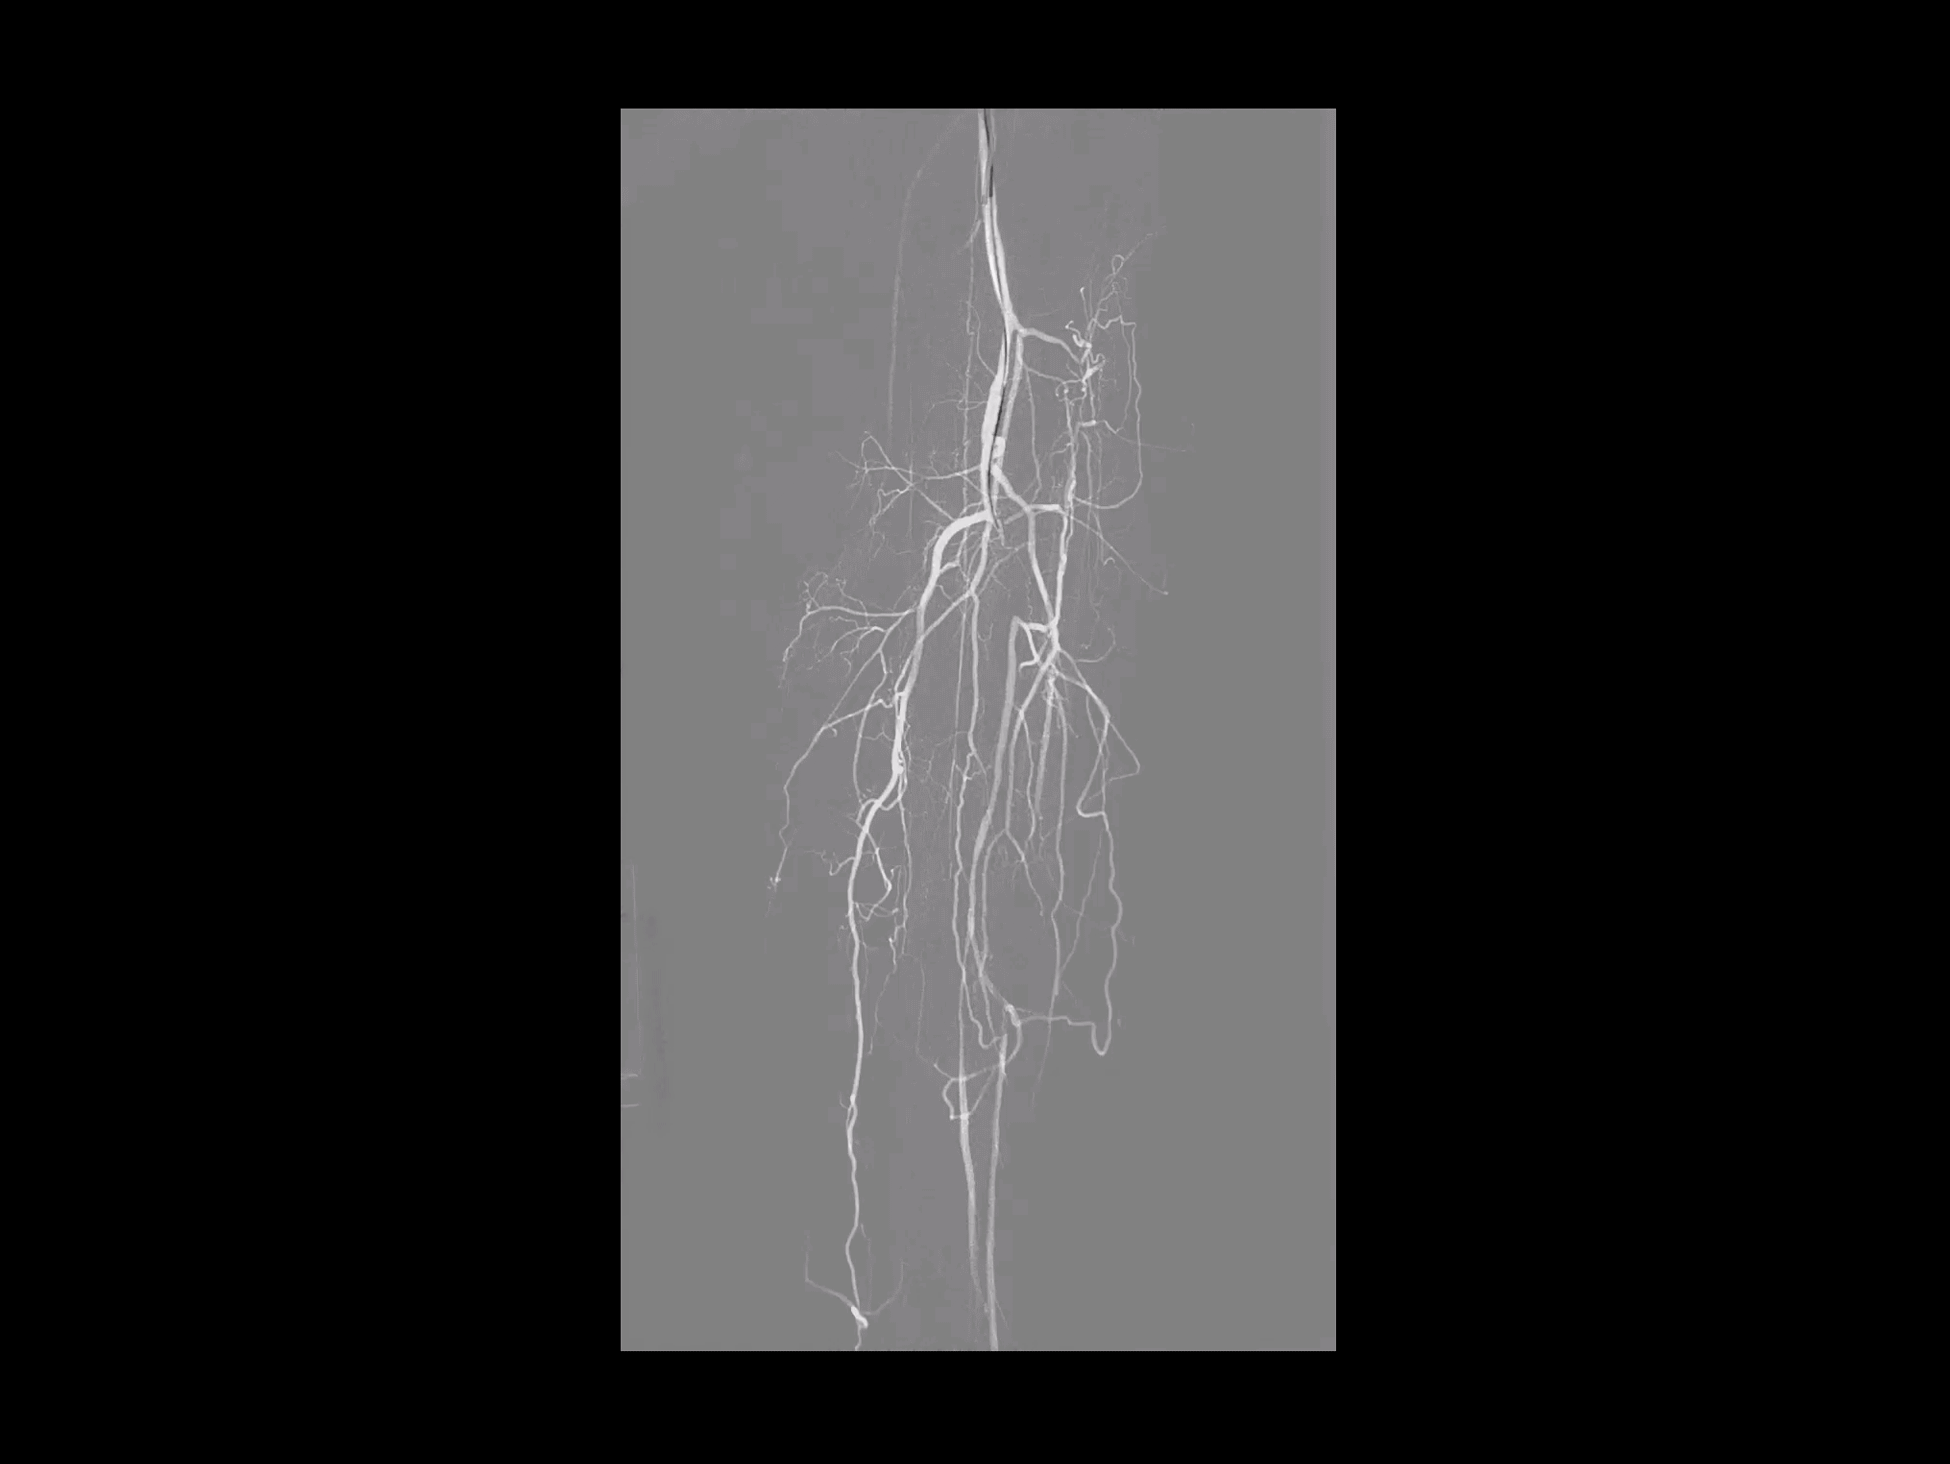

Radiologie intervențională

Hartă ghid

Ocluzia arterială a membrelor inferioare a fost tratată prin angioplastie transluminală percutanată, sub ghidajul precis oferit de funcția Roadmap.

uNavi

Suprapune imaginea DSA peste imaginea fluoroscopică live pentru un ghidaj precis în timpul procedurii.